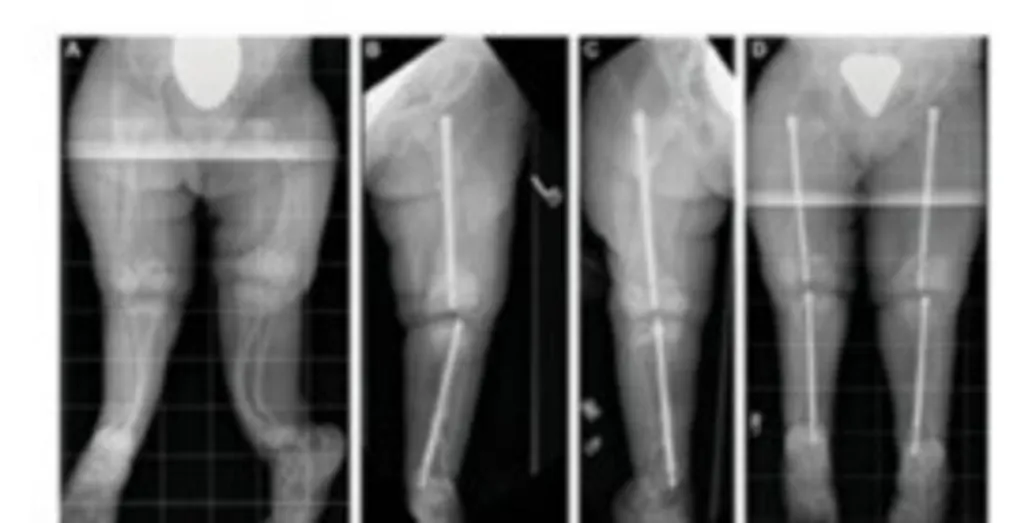

ഫിഗർ 8 (a, b)- ൽ കാണുന്ന രോഗി 18 വയസ്സുള്ള ഒരു എഞ്ചിനീയറിംഗ് വിദ്യാർത്ഥിയായിരുന്നു. ഒരു കാലിന് നീളം കുറവായതിനാൽ അദ്ദേഹത്തിന് ശരിയായി നടക്കാനോ ഓടാനോ കഴിയുന്നില്ലായിരുന്നു. ക്ലിനിക്കൽ പരിശോധനയ്ക്ക് ശേഷം, കാലിന്റെ നീളവ്യത്യാസം കൃത്യമായി വിലയിരുത്തുന്നതിനായി പൂർണ്ണനീളത്തിലുള്ള സ്റ്റാൻഡിംഗ് എക്സ്-റേ എടുത്തു. പരിശോധനയിൽ തുടയെല്ലിലും (Femur) കാൽഎല്ലിലും (Tibia) നീളം കുറവുണ്ടെന്ന് കണ്ടെത്തി.

ഈ രോഗിയിൽ ആദ്യം കാൽഎല്ലിന്റെ നീളം കൂട്ടുന്നതിനായി ഇലിസാരോവ് ഫ്രെയിം ഉപയോഗിക്കാൻ തീരുമാനിച്ചു. ക്ലിനിക്കൽ ചിത്രത്തിൽ കാണുന്നപോലെ, കാൽഭാഗത്ത് ഇലിസാരോവ് ഫ്രെയിം ഘടിപ്പിച്ചു.

(a,ശസ്ത്രക്രിയയ്‌ക്ക് മുൻപുള്ള പൂർണ്ണനീള എക്സ്-റേ – b,ഫ്രെയിം ഘടിപ്പിച്ചശേഷമുള്ള ചിത്രം : Fig 8 a,b)